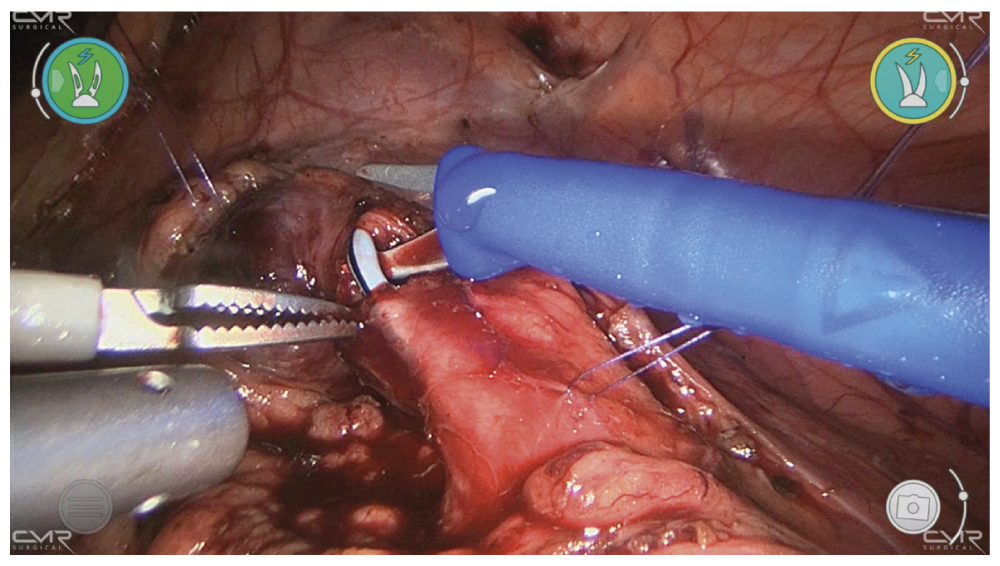

Камень размером 18 × 10 мм визуализирован и извлечён из просвета мочеточника с использованием окончатого атравматичного зажима (рис. 4). Затем он погружён в палец латексной перчатки, доставленной к месту выполнения процедуры, и извлечён наружу. Через катетер, введённый через просвет мочеточника, промывался сам мочеточник и почечная лоханка физиологическим раствором, чтобы удалить фрагменты камней. Конец стента, установленного в мочеточнике, продвинут вверх до уровня почечной лоханки. Продольная уретеротомия закрыта в поперечном направлении путём наложения отдельных абсорбирующихся швов (рис. 5). Рядом с линией швов оставляли дренажный катетер.

Рис. 5. Робот-ассистированная уретеролитотомия. Этап поперечной уретеропластики.

Fig. 5. Robot-assisted ureterolithotomy. Transverse urethroplasty.